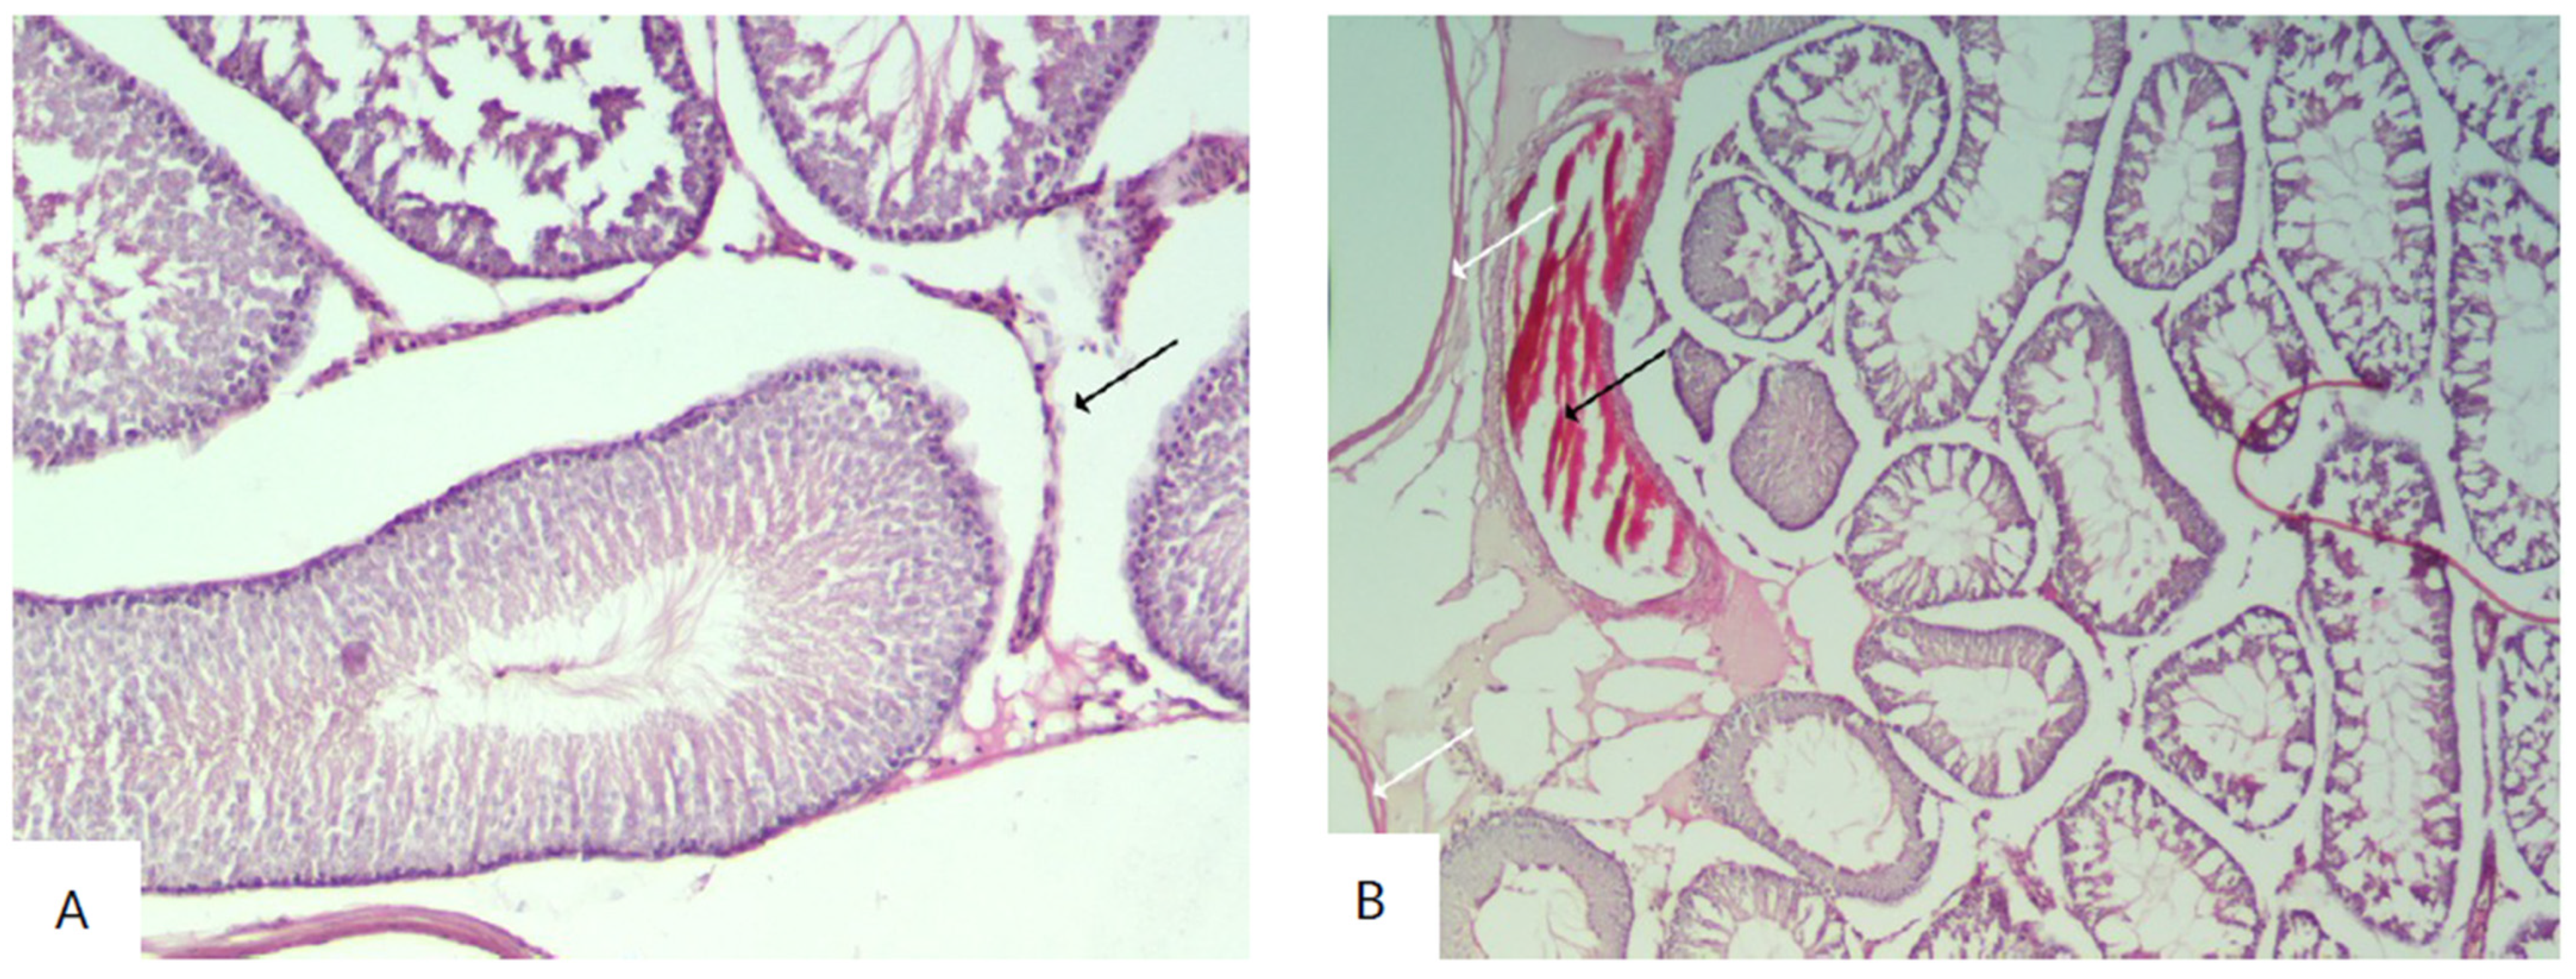

3. Results